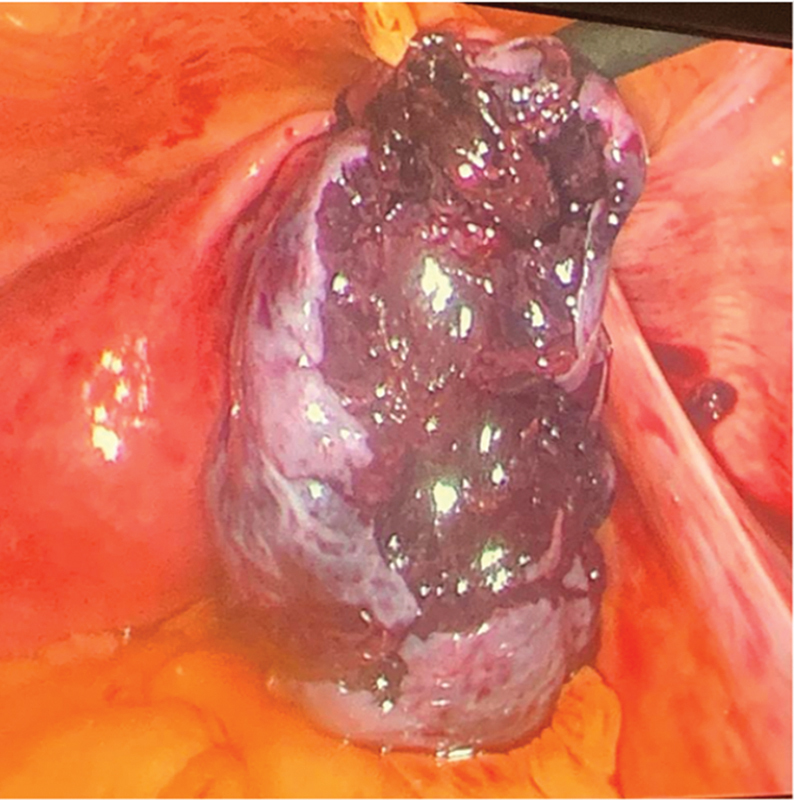

卵巢扭转是妇科急症之一,手术治疗是挽救卵巢的标准方法,同时也能发现一些意外的解剖缺陷,这些缺陷会增加卵巢扭转的风险。我们报告了一例因怀疑卵巢扭转而接受腹腔镜诊断的 27 岁单身女性病例。术中,我们发现右侧附件扭转(卵巢和输卵管),右侧卵巢和输卵管嵌顿在位于右侧子宫骶骨韧带内侧的大腹膜囊中。使用非创伤性腹腔镜镊子将肿胀的附件剥离并小心拉至大腹膜囊外侧。左侧附件正常。患者进行了第二次腹腔镜检查,计划对大腹膜缺损进行腹膜闭合。以前曾有两例报告过卵巢嵌顿,但与卵巢扭转无关,也不涉及腹膜闭合,与我们报告的卵巢剥离和腹膜缺损闭合不同。这种情况的病因可能是先天性的,因为没有其他明显的病因,如盆腔创伤、既往手术、盆腔炎或子宫内膜异位症。我们的临床评估表明,腹膜囊可以防止卵巢自发剥离,从而加强卵巢扭转的进程,使其在被困在腹膜囊中时发生缺血性病变。这种情况会导致囊壁之间的细胞受压,随后组织水肿,从而增强缺血效应。

Ovarian torsion is one of the gynecological emergencies and surgical intervention is the standard management for ovarian salvage as well as reveals some unexpected anatomical defects that increase the risk of ovarian torsion. We report a case of a 27-year-old single, nulliparous female taken for diagnostic laparoscopy with suspicion of ovarian torsion. Intraoperatively, we found right adnexa torsion (ovary with tube) along with incarceration of the right ovary and tube into the big peritoneal sac, which was located medial to the right uterosacral ligament. Detorsion and careful pulling of the swollen adnexa were done to the outside of the big peritoneal sac using nontraumatic laparoscopic forceps. The left side was normal with normal left adnexa. The patient had a second laparoscopic look with a plan for peritoneal closure of the big peritoneal defect. There are two cases which have previously reported ovarian incarceration, but were not associated with ovarian torsion, and did not involve peritoneal closure unlike our report of ovarian detorsion and peritoneal defect closure. The etiology of this condition is thought to be likely congenital as there were no other visible etiologies like pelvic trauma, previous surgery, pelvic inflammatory disease, or endometriosis. Our clinical assessment suggests that a peritoneal sac can enhance the course of ovarian torsion to involve ischemic changes of the ovary when trapped inside of it, by its prevention of spontaneous detorsion. This condition will result in the compression of the cells between the sac wall and subsequent tissue edema enhancing the ischemic effect.